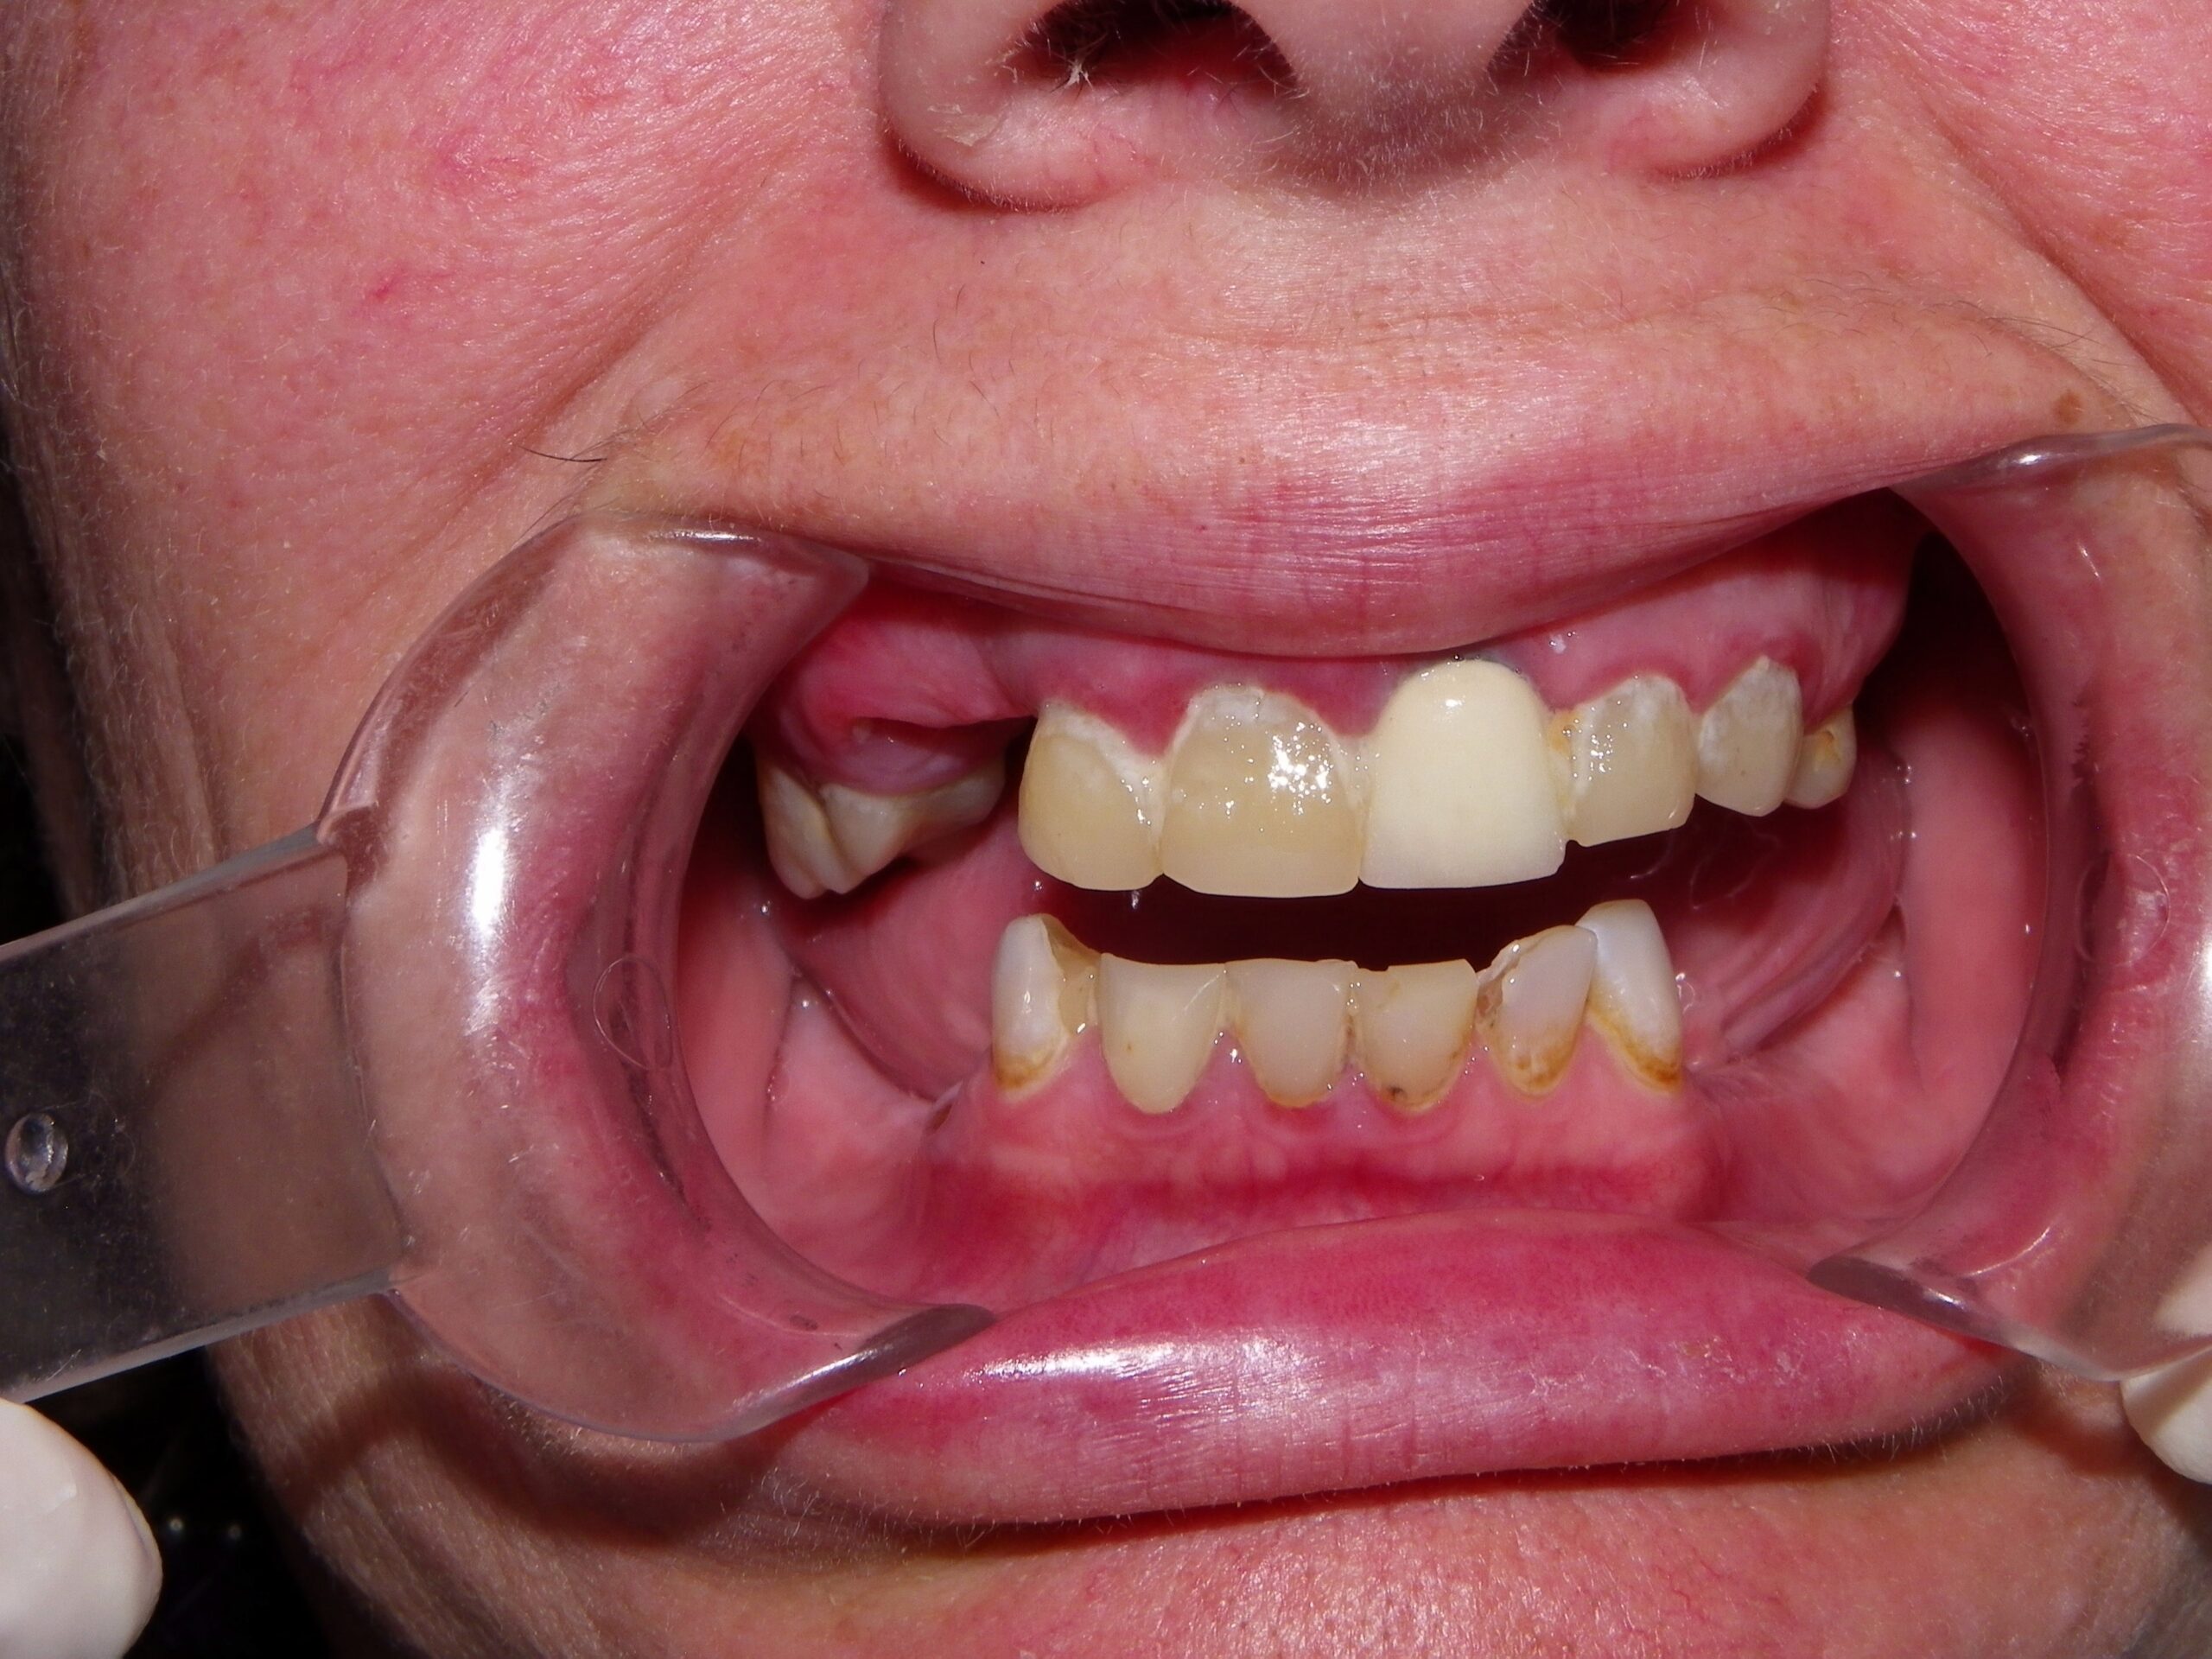

These natural teeth are non-restorable, but with the technology available we provided a very functional and esthetic result. The case was treatment planned using a fully guided implant system, Nobel Biocare. The maxilla (upper) are supported by 4 implants. This technique is referred to as the All-on-4. The maxilla is a screw retained wrap around prosthetic and removed only by a dental professional. The patient will have the teeth removed and placed back onto the implants every 12-18 months. This is an easy appointment done in less then an hour. This prosthetic is as close to having natural teeth as a patient can get. The mandibular teeth (lower) are supported by 4 implants. This lower denture is removable and the patient doesn’t sleep with this in their mouth at night. This type of denture is more of a traditional denture but because it is implant supported the patient is able to function as close to normal as possible. The outcome was very predictable because of the technology Dr. Dove has invested in. This provides our patients with a very great service.

Before: